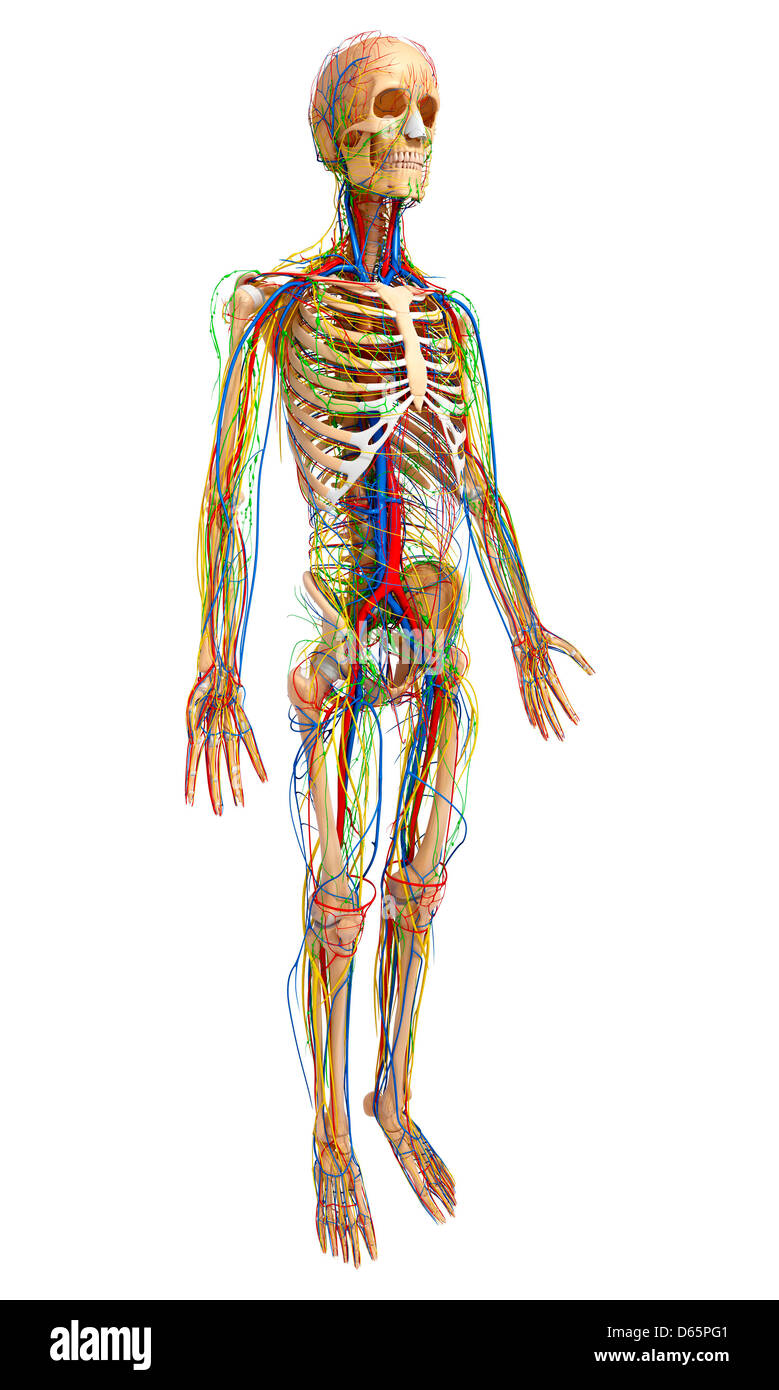

Male anatomy, artwork Banque D'Imageshttps://www.alamyimages.fr/image-license-details/?v=1https://www.alamyimages.fr/photo-image-male-anatomy-artwork-55446497.html

Male anatomy, artwork Banque D'Imageshttps://www.alamyimages.fr/image-license-details/?v=1https://www.alamyimages.fr/photo-image-male-anatomy-artwork-55446497.htmlRFD65PG1–Male anatomy, artwork